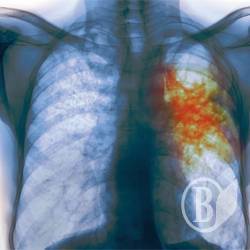

Одна из воспитательниц черниговского детсада №22 оказалась больной открытой формой туберкулеза.

«А в мае она оказалась больной открытой формой туберкулеза, хотя эта стадия длится от 6 до 10 месяцев. Врачи же на собрании заверяли, что она только что заболела», - пишет Виктория Пискун.